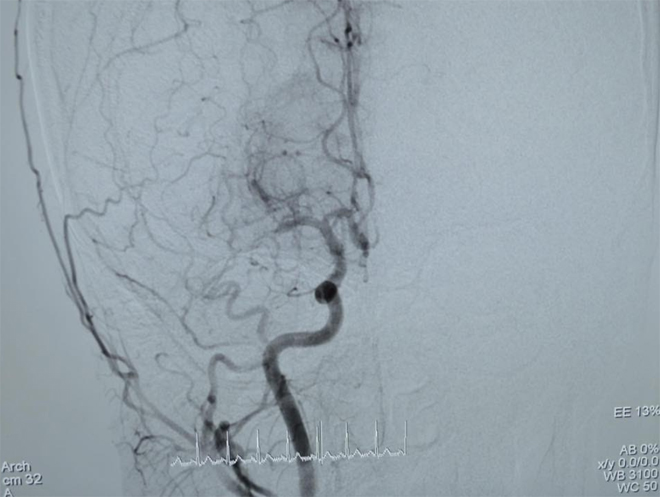

![]() |

| Hình ảnh trước khi can thiệp lấy huyết khối mạch máu não cho bệnh nhân T.. |